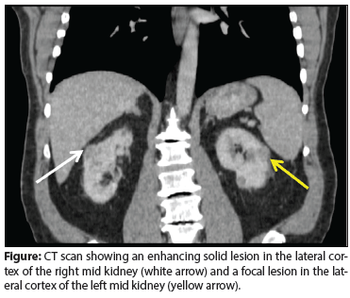

A 69-year-old man presented in the urology clinic for evaluation of bilateral renal masses, discovered incidentally during routine exams for follow-up of his chronic kidney disease.